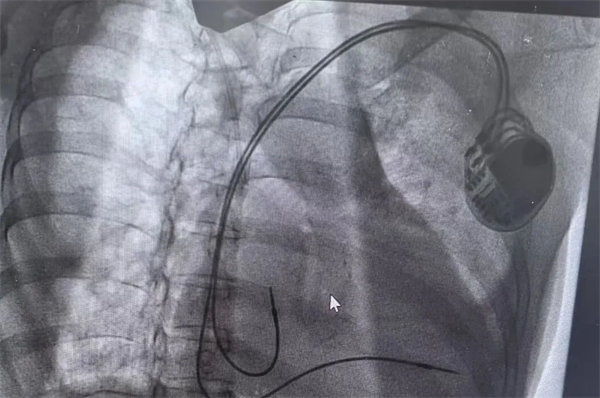

患者转入重症医学科心电监护提示间歇性三度房室传导阻滞、室性心动过速,同时合并心源性休克。心血管内一科陈万林副主任医师急会诊后考虑三度房室传导阻滞是患者发生意识丧失的元凶。立即行床旁临时起搏器植入术,快速植入临时起搏器后患者再未出现恶性心律失常。

在充分术前准备和家属的理解支持下,心血管内一科主任翟向伟副主任医师、陈万林副主任医师及介入导管室团队为患者实施了双腔心脏永久性起搏器植入术。通过左侧腋静脉入路,精准、轻柔操作顺利植入起搏器。术后经过医护团队的精细诊治,起搏器囊袋如期愈合,患者可自由活动,生活质量得到有效改善。患者及家属露出了久违的笑容。